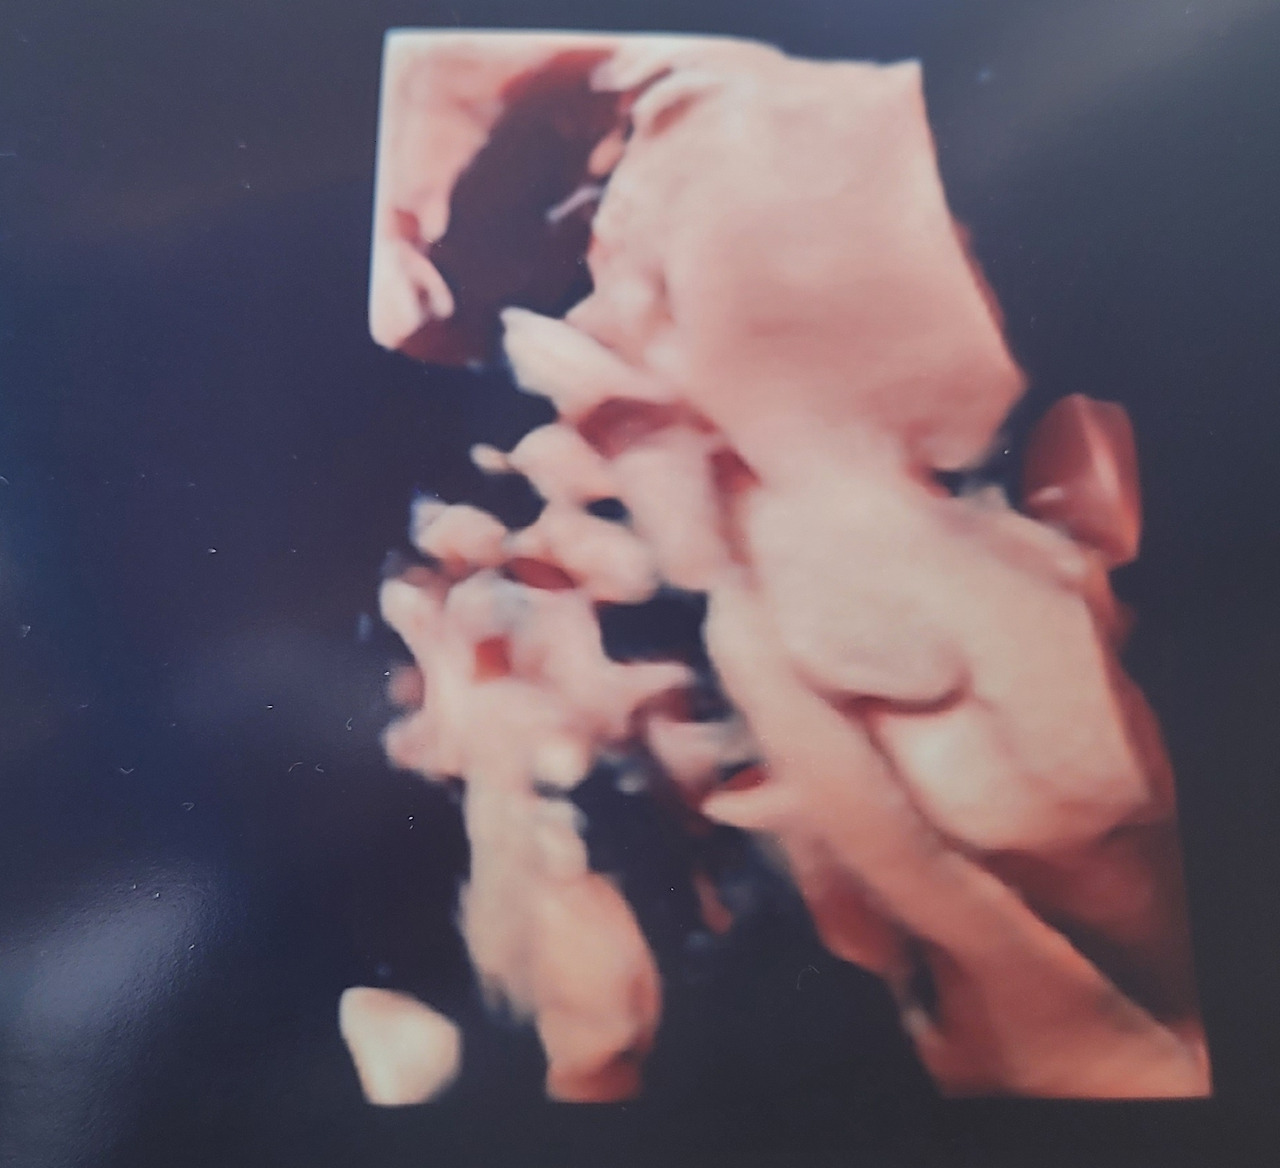

우리 아이는 귀엽게도 미소 짓고 있었다.

"아이가 웃고 있네요."

웃는 모습이 남편을 꼭 닮았다.

그렇게 기다렸던 남편을 꼭 닮은 아들을 만날 시간이 가까워진다.